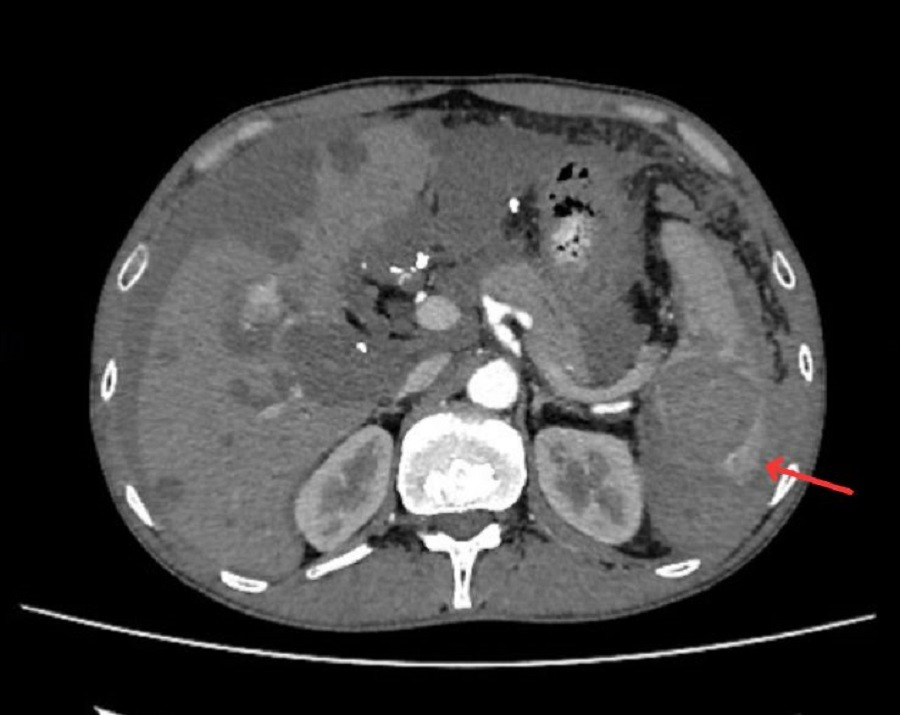

Hình ảnh kiểm tra phát hiện vị trí lách của bệnh nhân bị vỡ

Ngay sau khi tiếp nhận bệnh nhân, các bác sĩ đã tiến hành truyền dịch, giảm đau và chỉ định chụp MSCT vùng bụng. Kết quả cho thấy, anh bị vỡ lách độ IV. Đây là tình trạng vỡ lách mức độ nặng, có nguy cơ chảy máu ồ ạt vào ổ bụng khiến bệnh nhân tử vong vì mất máu cấp.